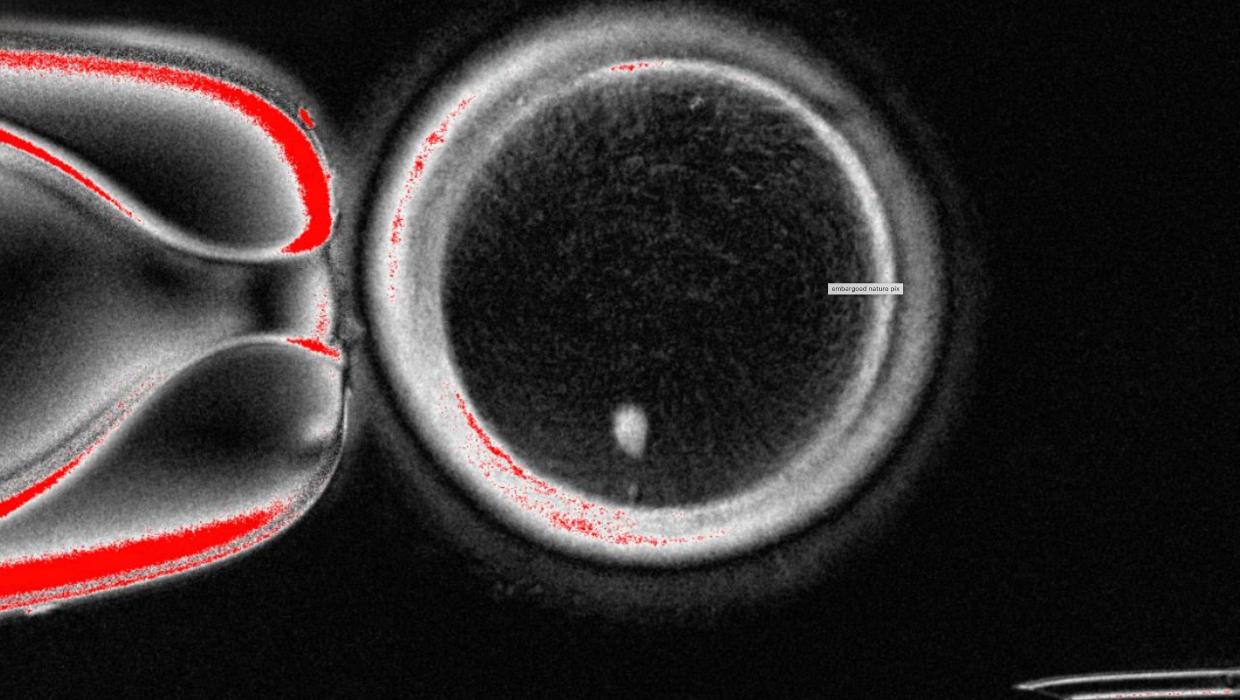

Researchers in the United States have successfully transformed human skin cells into fertilizable eggs, marking a significant advancement in reproductive science. This breakthrough could pave the way for the development of lab-grown eggs and sperm, offering new possibilities for individuals and couples facing fertility challenges.

The study, conducted by a team at the University of California, Los Angeles, was published in a leading scientific journal in 2023. By reprogramming skin cells into pluripotent stem cells, the researchers created gametes that can potentially be fertilized. This innovative approach represents a crucial milestone in the ongoing quest to assist those who are unable to conceive naturally.

The process involved turning mature skin cells into induced pluripotent stem cells, which were then guided to develop into egg cells. This method not only provides a new avenue for generating gametes but also raises questions about the ethical considerations surrounding reproductive technology.

While this research represents a promising step forward, further studies are necessary to ensure the safety and efficacy of the lab-grown eggs. Researchers will need to explore how these eggs can be successfully fertilized and developed into viable embryos.